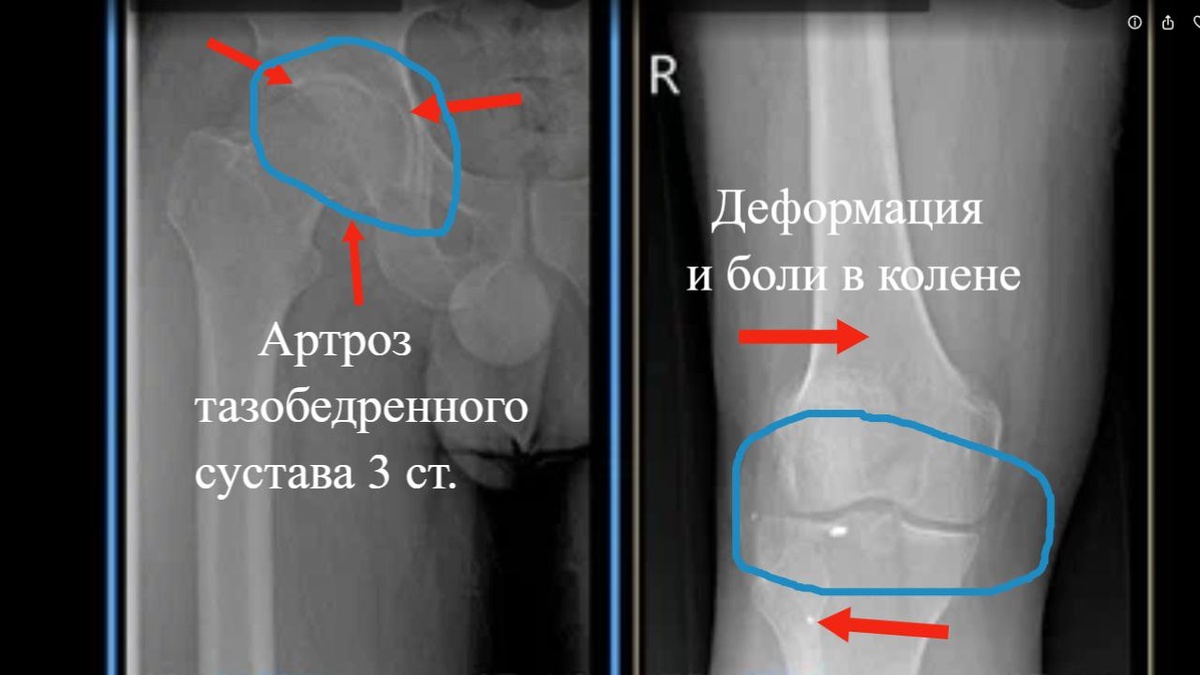

‼️Почему болит коленный сустав при артрозе тазобедренного сустава. И что делать? 1️⃣Часто за помощью обращаются пациенты с болями в коленном суставе и отсутствием эффекта от лечения коленного сустава препаратами гиалуроновой кислоты (флексотрон, армавискон, остенил, синвиск, гиастат и др.), на которое они потратили десятки тысяч рублей. 2️⃣Во всех случаях боли в коленном суставе, необходимо обследование тазобедренного сустава, а не только коленного сустава. 3️⃣При тяжёлых артрозах тазобедренного сустава (фото слева), развивается приводящая контрактура тазобедренного сустава. У человека нет полного объёма движений в суставе и бедро смещается кнутри. 4️⃣А голень смещается кнаружи, что называется вальгусная деформация коленного сустава. (фото справа) Нарушаются правильные нагрузки на кости, образующие коленный сустав, что и приводит к болям в суставе и отсутствии эффекта от лечения дорогими препаратами. 5️⃣Что делать ? В показанном мною случае, необходимо эндопротезирование тазобедренного сустава. 6️⃣При боли в коленном суставе всегда обращайтесь к опытному ортопеду. ❗️Запись на консультацию +7931-271-03-03 или на сайте centerto.com #тазобедренныйсустав #артроз #коленныйсустав